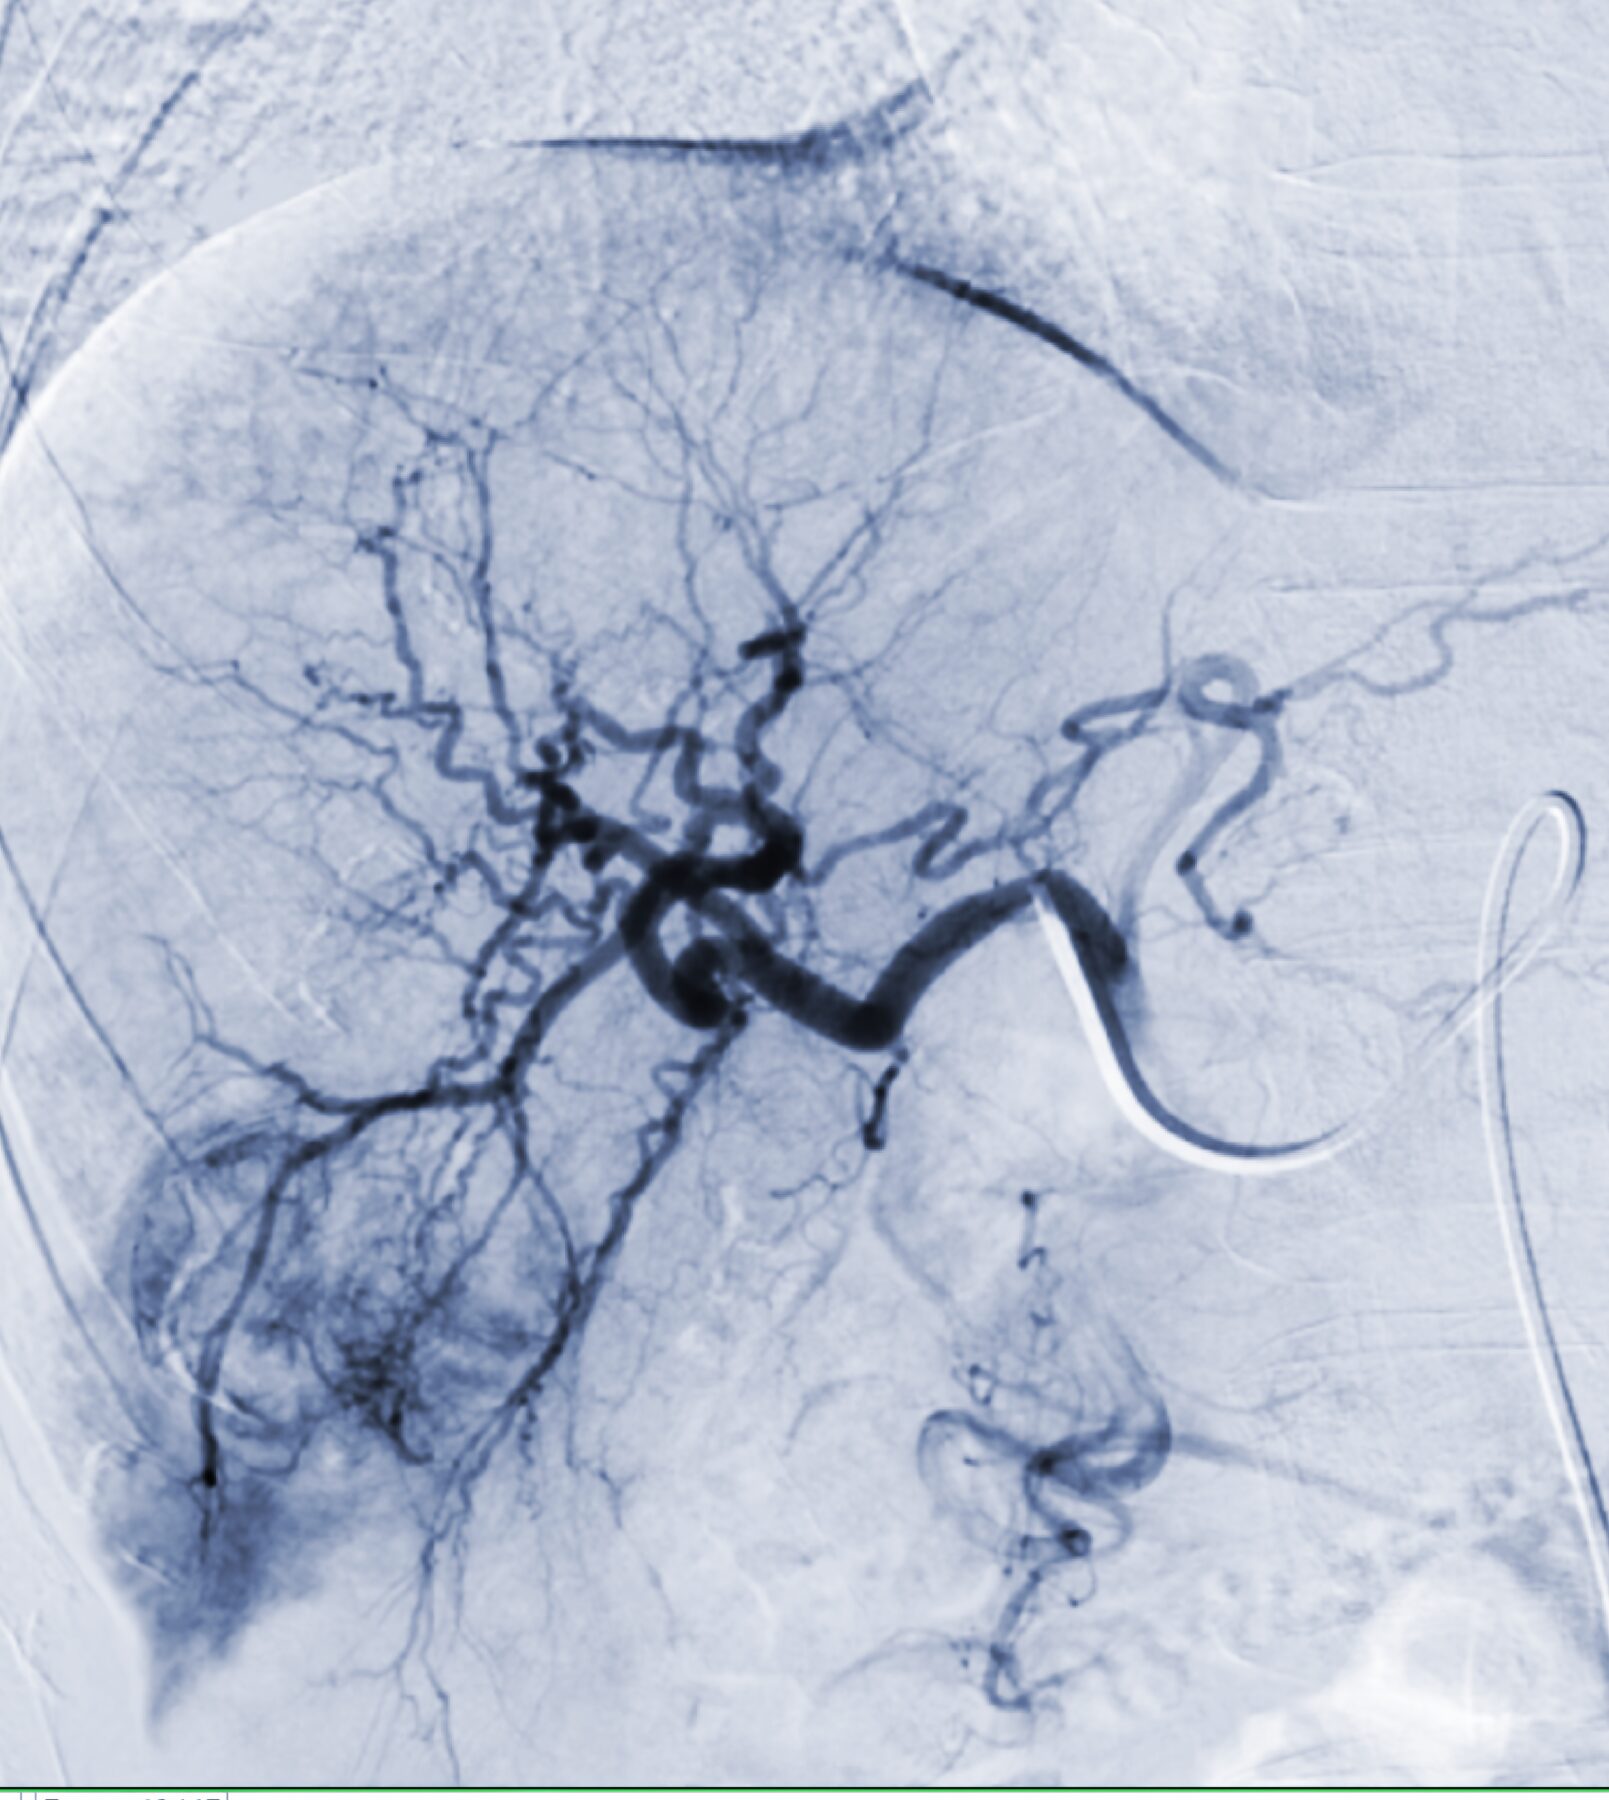

From microbubbles to shorter hospital stays – Jim Zhong takes us through the incredible world of interventional oncology…| Cancer Research UK - Cancer News